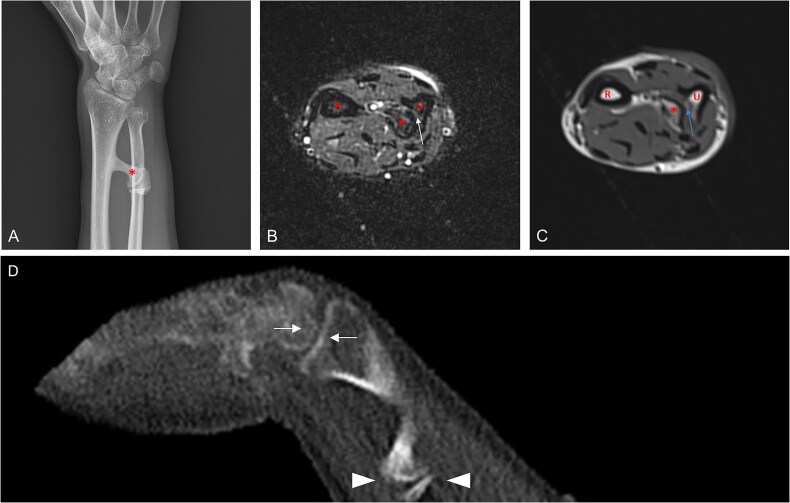

假关节(假关节)是正常异位骨骼骨折愈合的并发症,但在异位部位未见报道。进行性骨化纤维发育不良(FOP)是一种极其罕见的遗传性疾病,其特征是进行性异位骨化(HO)和先天性骨骼异常,包括正常位置骨骼的发育性关节病。在这里,我们报告了6例FOP患者的异位假关节形成,所有这些患者都发生在疼痛发作和膝关节、髋关节和前臂软结缔组织的HO之后。据我们所知,FOP是唯一发生异位假关节形成的人类疾病。这些发现支持来自突变ACVR1的BMP通路信号失调不仅介导HO,还介导异位假关节的形成,并且异位假关节可以由新生的肌肉骨骼元件引起。

Pseudoarthroses (false joints) occur as a complication of fracture healing in the normotopic skeleton but have not been reported at ectopic sites. Fibrodysplasia ossificans progressiva (FOP) is an ultra-rare genetic disorder characterized by progressive heterotopic ossification (HO) and congenital skeletal abnormalities including developmental arthropathy in the normotopic skeleton. Here, we report ectopic pseudojoint formation in 6 patients with FOP, all occurring after painful flare-ups and HO in soft connective tissues of the knee, hip, and forearm. To our knowledge, FOP is the only human condition in which ectopic pseudojoint formation occurs. These findings support that dysregulated BMP pathway signaling from mutant ACVR1 mediates not only HO, but also ectopic pseudojoint formation, and that ectopic pseudojoints can arise from de novo musculoskeletal elements.